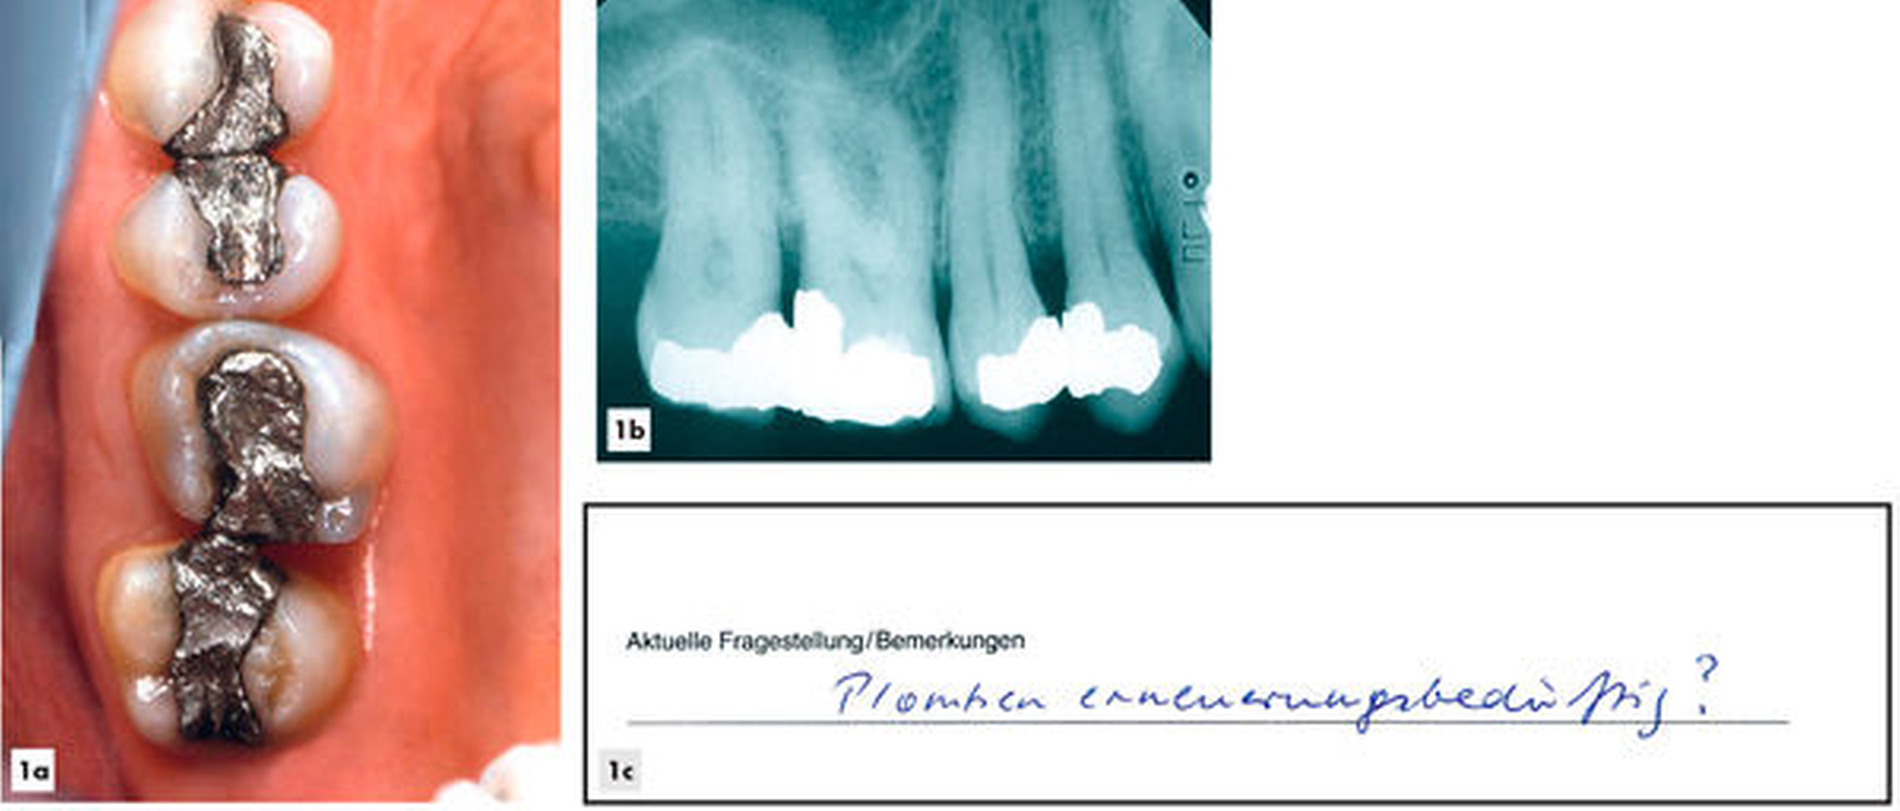

In Abbildung 1 werden etwa 30 Jahre alte Amalgamrestaurationen einer 60-jährigen Patientin gezeigt. Die Patientin wünschte eine Beratung mit der Frage: „Plomben erneuerungsbedürftig?“. Eine klinische und röntgenografische Untersuchung ergab keine Hinweise auf klinisch relevante Schäden, die ein sofortiges Eingreifen erforderlich gemacht hätten. Die Patientin wurde darüber aufgeklärt, dass bei ihr ein erhöhtes Risiko für Frakturen an den Restaurationen oder an den Zahnhartsubstanzen bestehe, die man allerdings im Eintrittsfall restaurativ angehen könne. Sie favorisierte zunächst ein Monitoring (Belassen und Beobachten). Acht Jahre später wurde wegen einer Randleistenfraktur eines Molaren eine Reparaturrestauration eingebracht (Abbildung 2). Sechzehn Jahre später wurden zwei weitere kleine Korrekturen vorgenommen (Abbildung 3). Nach 20 Jahren (Abbildung 4) war die nunmehr 80-jährige Patientin mit ihren inzwischen circa 50 Jahre alten Amalgamfüllungen immer noch sehr zufrieden. Vor diesem Hintergrund erscheint es angebracht, Restaurationen nicht voreilig als „insuffizient“ zu betrachten.

Abbildungen 1–4: Nachbeobachtungen und Reparaturen bei 30 Jahre alten Amalgamrestaurationen über einen Zeitraum von weiteren 20 Jahren

Ausgangssituation